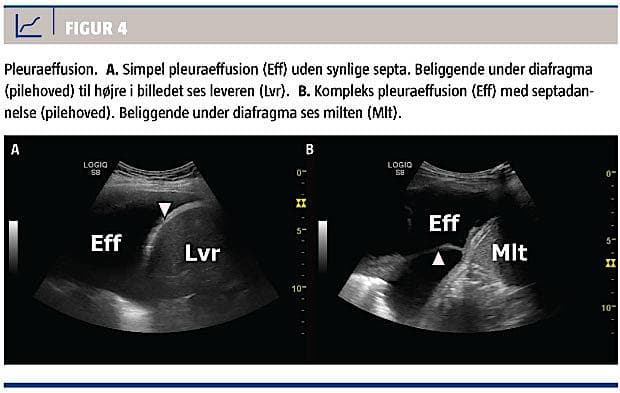

Parapneumonisk effusion og empyem

LUS giver en meget høj diagnostisk præcision ved diagnostik af pleuraeffusion, der er en hyppig komplikation i forbindelse med pneumoni [17]. Ved forekomst af pleuraeffusion med septa hos en patient med pneumoni, bør man have kompliceret parapneumonisk effusion og empyem in mente (Figur 4) [18, 19].